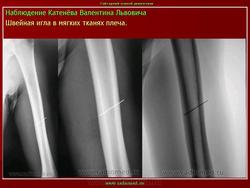

Металлическая игла в молочной железе

Швейная игла